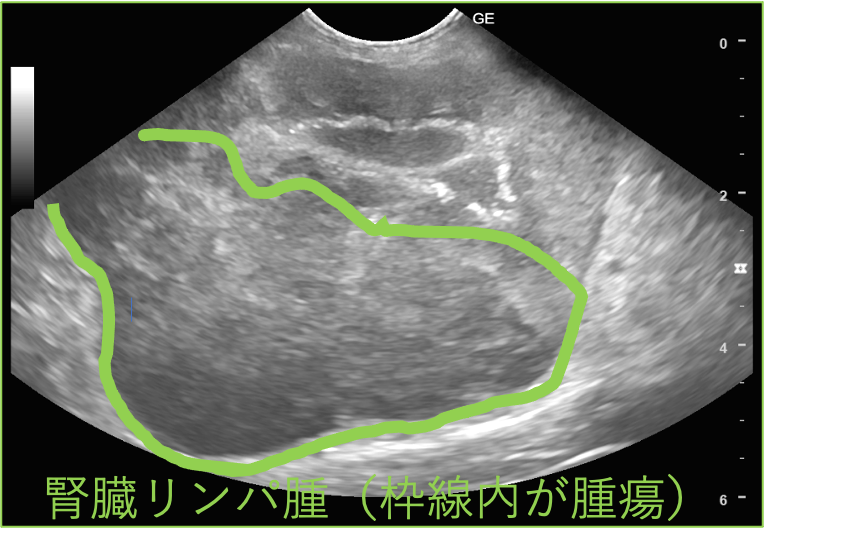

超音波検査画像(雑種猫、3歳)

多くの悪性腫瘍は上記の画像のように、腫瘤(塊)を形成します。

実際に、化学療法を実施した猫の超音波検査画像を記載しました。

化学療法実施前は、腎臓に明らかな腫瘤病変が認められましたが

化学療法実施1週間後には、腫瘤病変はほぼ確認できない程に退縮しています。

超音波検査画像 猫 MIX 3歳 腎臓リンパ腫 化学療法実施前